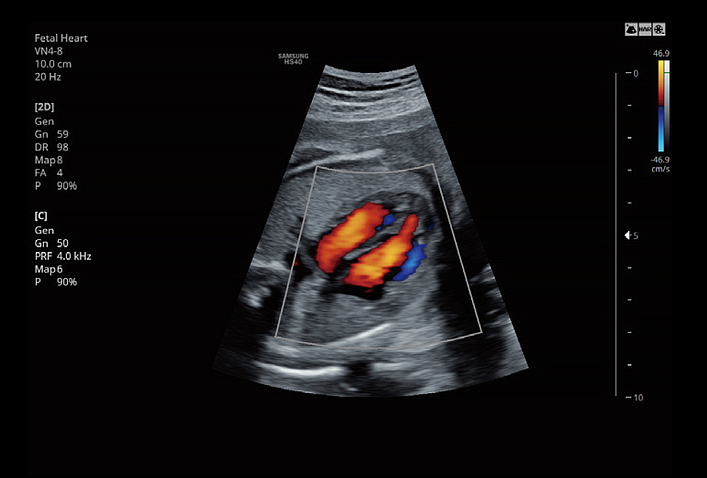

VN4-8Application:Abdomen, Obstetrics, Gynecology, Musculoskeletal, Pediatric, Vascular, Urology |